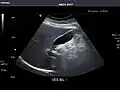

Left kidney -